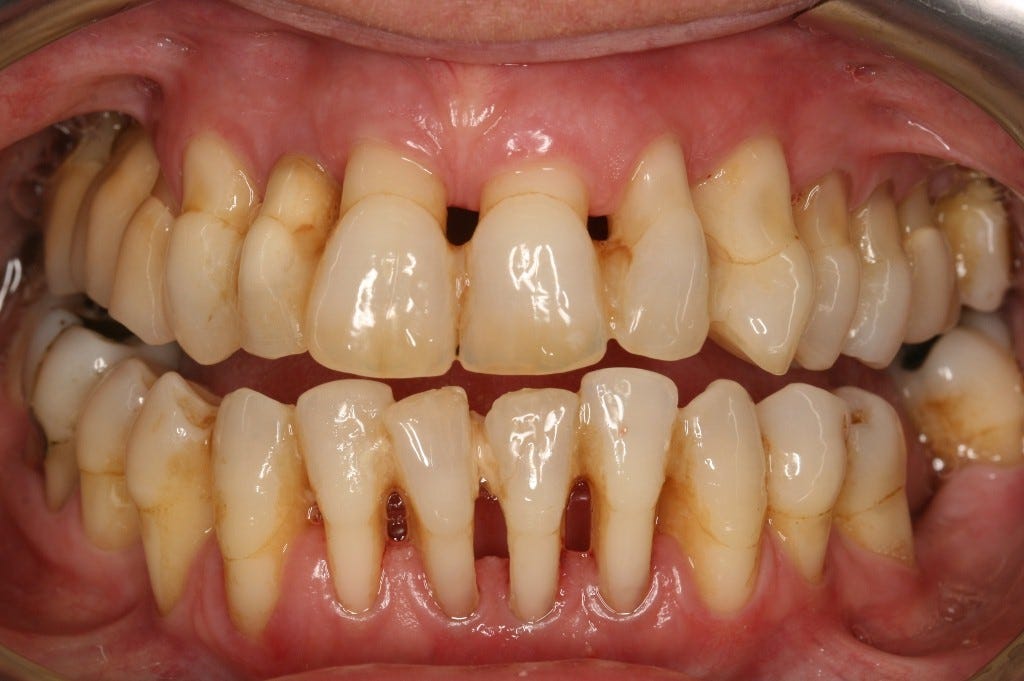

Get Periodontal Bone Loss Images. In periodontal disease, not only does the bone that supports the teeth, known as alveolar bone, reduce in height in relation to the teeth, but the morphology of the remaining alveolar bone is altered. Bone loss is most commonly associated with the following diseases:

Inflammation and bone loss are hallmarks of periodontal disease (pd). Horizontal bone loss is the most common pattern ol bone loss in periodontal disease. It can normally be prevented through good oral hygiene.

Radiographic indication of interproximal bone loss occurs when the distance between the cej and the alveolar the percentage of subjects with periodontal bone loss was computed for each age bracket. Title radiographic alveolar bone loss in patients. Accumulated evidence demonstrates that pd involves bacterially derived factors. The bacteria responsible for periodontitis can enter your bloodstream through gum tissue, possibly affecting other parts of your body.